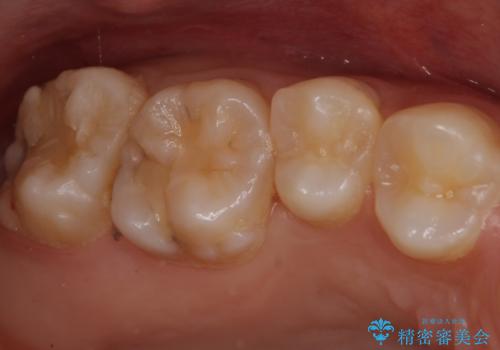

親知らずの手前の歯 抜歯後に適合の良いインレーでの修復処置

- 矯正前の虫歯治療をした患者様です。

親知らずに面している歯の一部が深いところまでかなり脆くなってしまっていたため(広範囲での脱灰)、親知らずの抜歯後に精度の良いインレーを装着していきました。